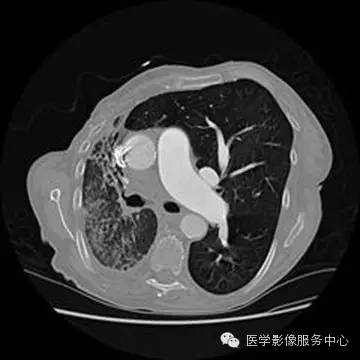

影像表现:

UAPA典型X线表现为患侧肺纹理稀疏肺、容积减小和透光度减低;患侧肺动脉段缺如对诊断UAPA具有重要提示意义,但由于肺纹理稀疏如诊断经验不足多不能明确此征象。胸部X线平片提示病变后,应首选胸部CT平扫进一步检查。

胸部CT平扫显像能力优于X线平片,显示UAPA典型征象更明显,偶尔可见患侧肺动脉段缺如。当见患侧失去正常肺小叶结构时,提示原发病导致肺泡发育障碍;另外可见肺纹理纤细走行僵直、肺门菲薄,可伴发肺大泡、间质改变及其他肺部病变。